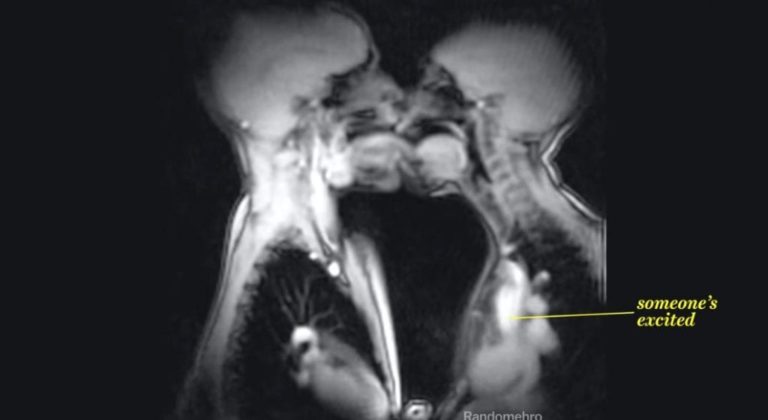

This video from Vox shows magnetic resonance imaging (MRI) scans of human beings doing all kinds of nifty things, like blowing a trumpet, drinking pineapple juice, giving birth, and even having sex. Watching a penis thrust into a vagina — or what I assume was a vagina — is far less erotic than you think; in fact, it almost appears violent. Far sweeter is when two people are showing kissing and the MRI scan revealed how fast one person’s heart is beating. It’s all very cool and that science dork sort of way. And you thought “Masters Of Sex” was impressive! [YouTube]